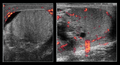

Decreased testicular power Doppler flow in the image on the left indicated torsion

| current | 12:57, 15 August 2016 | ![]() | 512 × 279 (207 KB) | Neil.m.young (Talk | contribs) | Decreased testicular power Doppler flow in the image on the left indicated torsion |